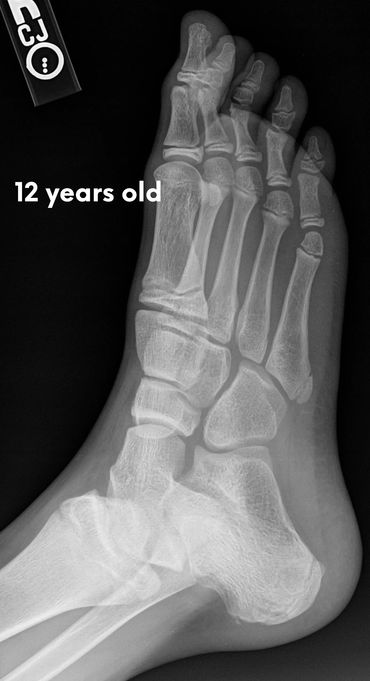

Let's check what their foot bones look like.

Pictures below will let you understand how babies' feet are developed.

Dear parents, children’s feet are developing structures, and the absence of an arch is a typical stage of development. The developing foot is not structurally ‘flat’; it is a highly compliant and plastic, that can respond to multiple factors, many of which we do not understand. Detailed X-RAY pictures above, let us understand that babies' foot bones are not connected till the teen years. Only at the age of 14, we may consider that the bones in the feet are developed and have reached their connections.

At the age of 18, we have fully completed foot structure, where muscles and bones create the whole support system.